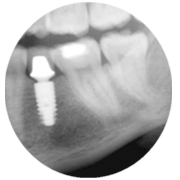

De unieke frictie lock en TissueCare-connectie creëren zo'n nauwkeurige verbinding tussen de twee componenten, dat subcrestale plaatsing van het implantaat mogelijk is. Dit leidt tot een positieve botrespons, waardoor het gewenste emergentieprofiel en de transgingivale genezing mogelijk worden.

Met andere woorden, Ankylos biedt de veelzijdigheid van een tweedelig systeem met behoud van gezond hard en zacht weefsel én het voorkomen van irritatie.